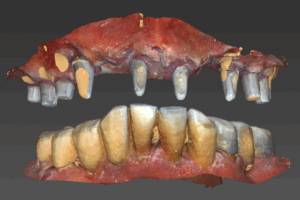

위쪽에 식립한 임플란트에 지대주를 연결한 모습입니다.

2번째 아래 수술 후 3개월 후에 방문하셔서 스캔바디 스캔을 해서 임플란트 위치를 확인하고 지대주와 지르코니아 보철 디자인을 했습니다.

스캔바디

지대주 디자인이 된 모습